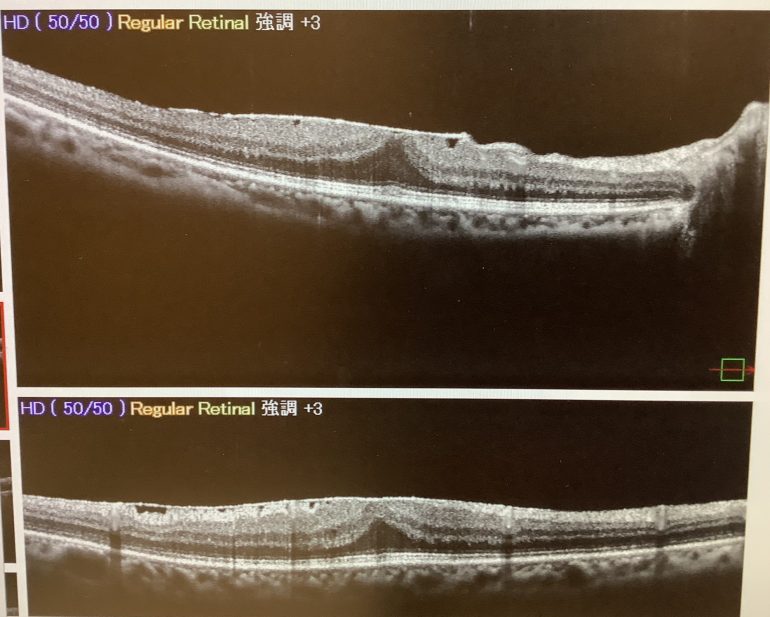

硝子体手術の方は2ヶ月前に白内障の手術を受けた60代の女性で、元々、黄斑上膜があるのは分かっていたのですが、まずは白内障の手術だけ行い、視力の改善が乏しかったり、歪みの自覚が強く出るようなら、改めて硝子体手術を行いましょうという事前の話し合いで、結果的に、白内障手術だけでは視力の改善が乏しく、今回、追加で硝子体手術をさせていただきました。

視力が下がっている場合、それが白内障のせいなのか、黄斑上膜のせいなのか、はたまた両方の影響なのかは、どちらか、もしくは両方がかなり進んでいれば、判断がしやすいですが、実際はなかなか難しい面もあります。

明らかに黄斑上膜が視力の低下に影響を及ぼしていると考えられれば、白内障と硝子体手術を一緒にした方が、すっきりすると思いますし、一回で手術が済み、楽な面もあると思います。ただ、白内障と硝子体手術を別にすること自体は全く問題はありませんので、黄斑上膜の影響がそれほどなさそうであれば、まずは白内障の手術だけして、その後の状況で黄斑上膜の硝子体手術をした方がよいかを考え、必要があれば追加で硝子体手術をするという方法も、不必要な手術を避ける意味で、よい方法だと思っています。